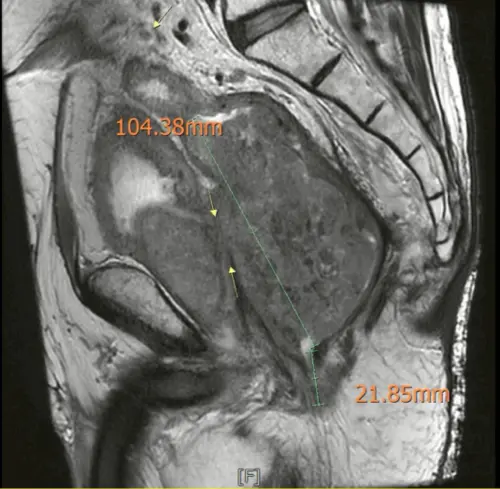

▲黃晟瑋醫師說明,從核磁共振影像顯示,王男腫瘤大小。(圖/黃晟瑋提供) 醫師說明,當直腸癌或其他骨盆腫瘤侵犯多個器官時,需要更大範圍的手術,即為骨盆複雜腫瘤根除手術,雖屬高難度手術,但在完整團隊與資源支持下,仍有機會達到完全切除腫瘤,甚至長期存活。